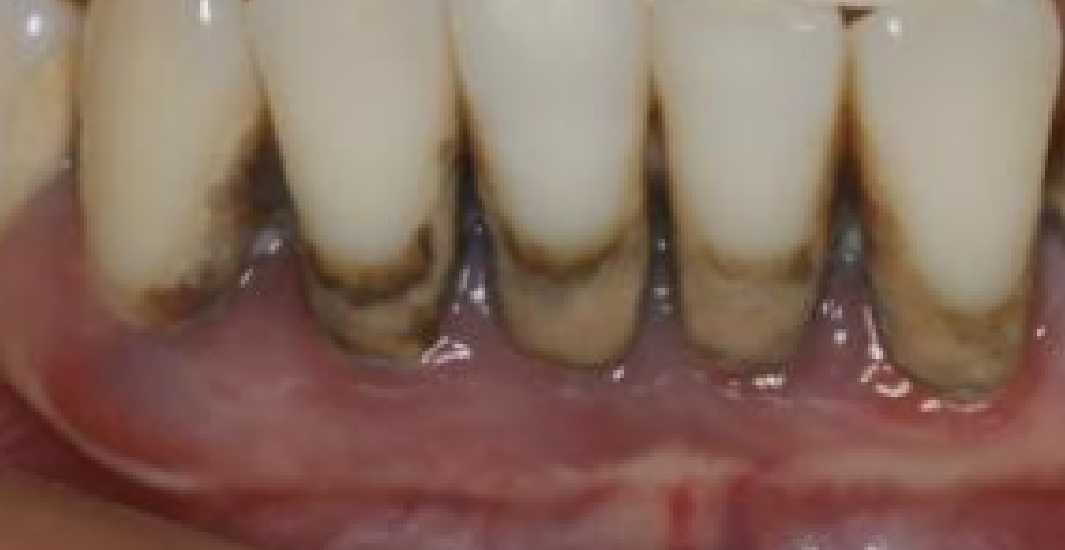

重度牙周色素沉着患者下前牙龈缘呈灰黑色(图片由医院提供)

“一些其他因素也可能导致牙龈出现类似‘铅线’的色素沉着,比如长期服用某些药物、牙龈局部炎症、色素沉着异常等,需要通过专业检查进行鉴别。”宫海环介绍,牙龈铅线与色素沉淀的本质区别在于:铅线是重金属中毒的特殊体征,表现为牙龈边缘灰暗色线状沉积;而色素沉淀多为饮食或口腔卫生导致的牙齿表面染色,无系统性健康危害。

宫海环介绍,牙龈“铅线”在医学上又称为“伯顿氏线”,是慢性重金属中毒过程中可能出现的一个较晚期的口腔体征,最常见于下颌前牙的唇侧牙龈。重金属在体内蓄积久了,会在牙齿和牙龈上有表现,最常见的是铅(灰黑色),其次是汞(灰蓝)、铋(蓝黑色)、银(黑色颗粒)。“铅线”随着量的增多,可能会突出到牙龈外边,到牙齿上。